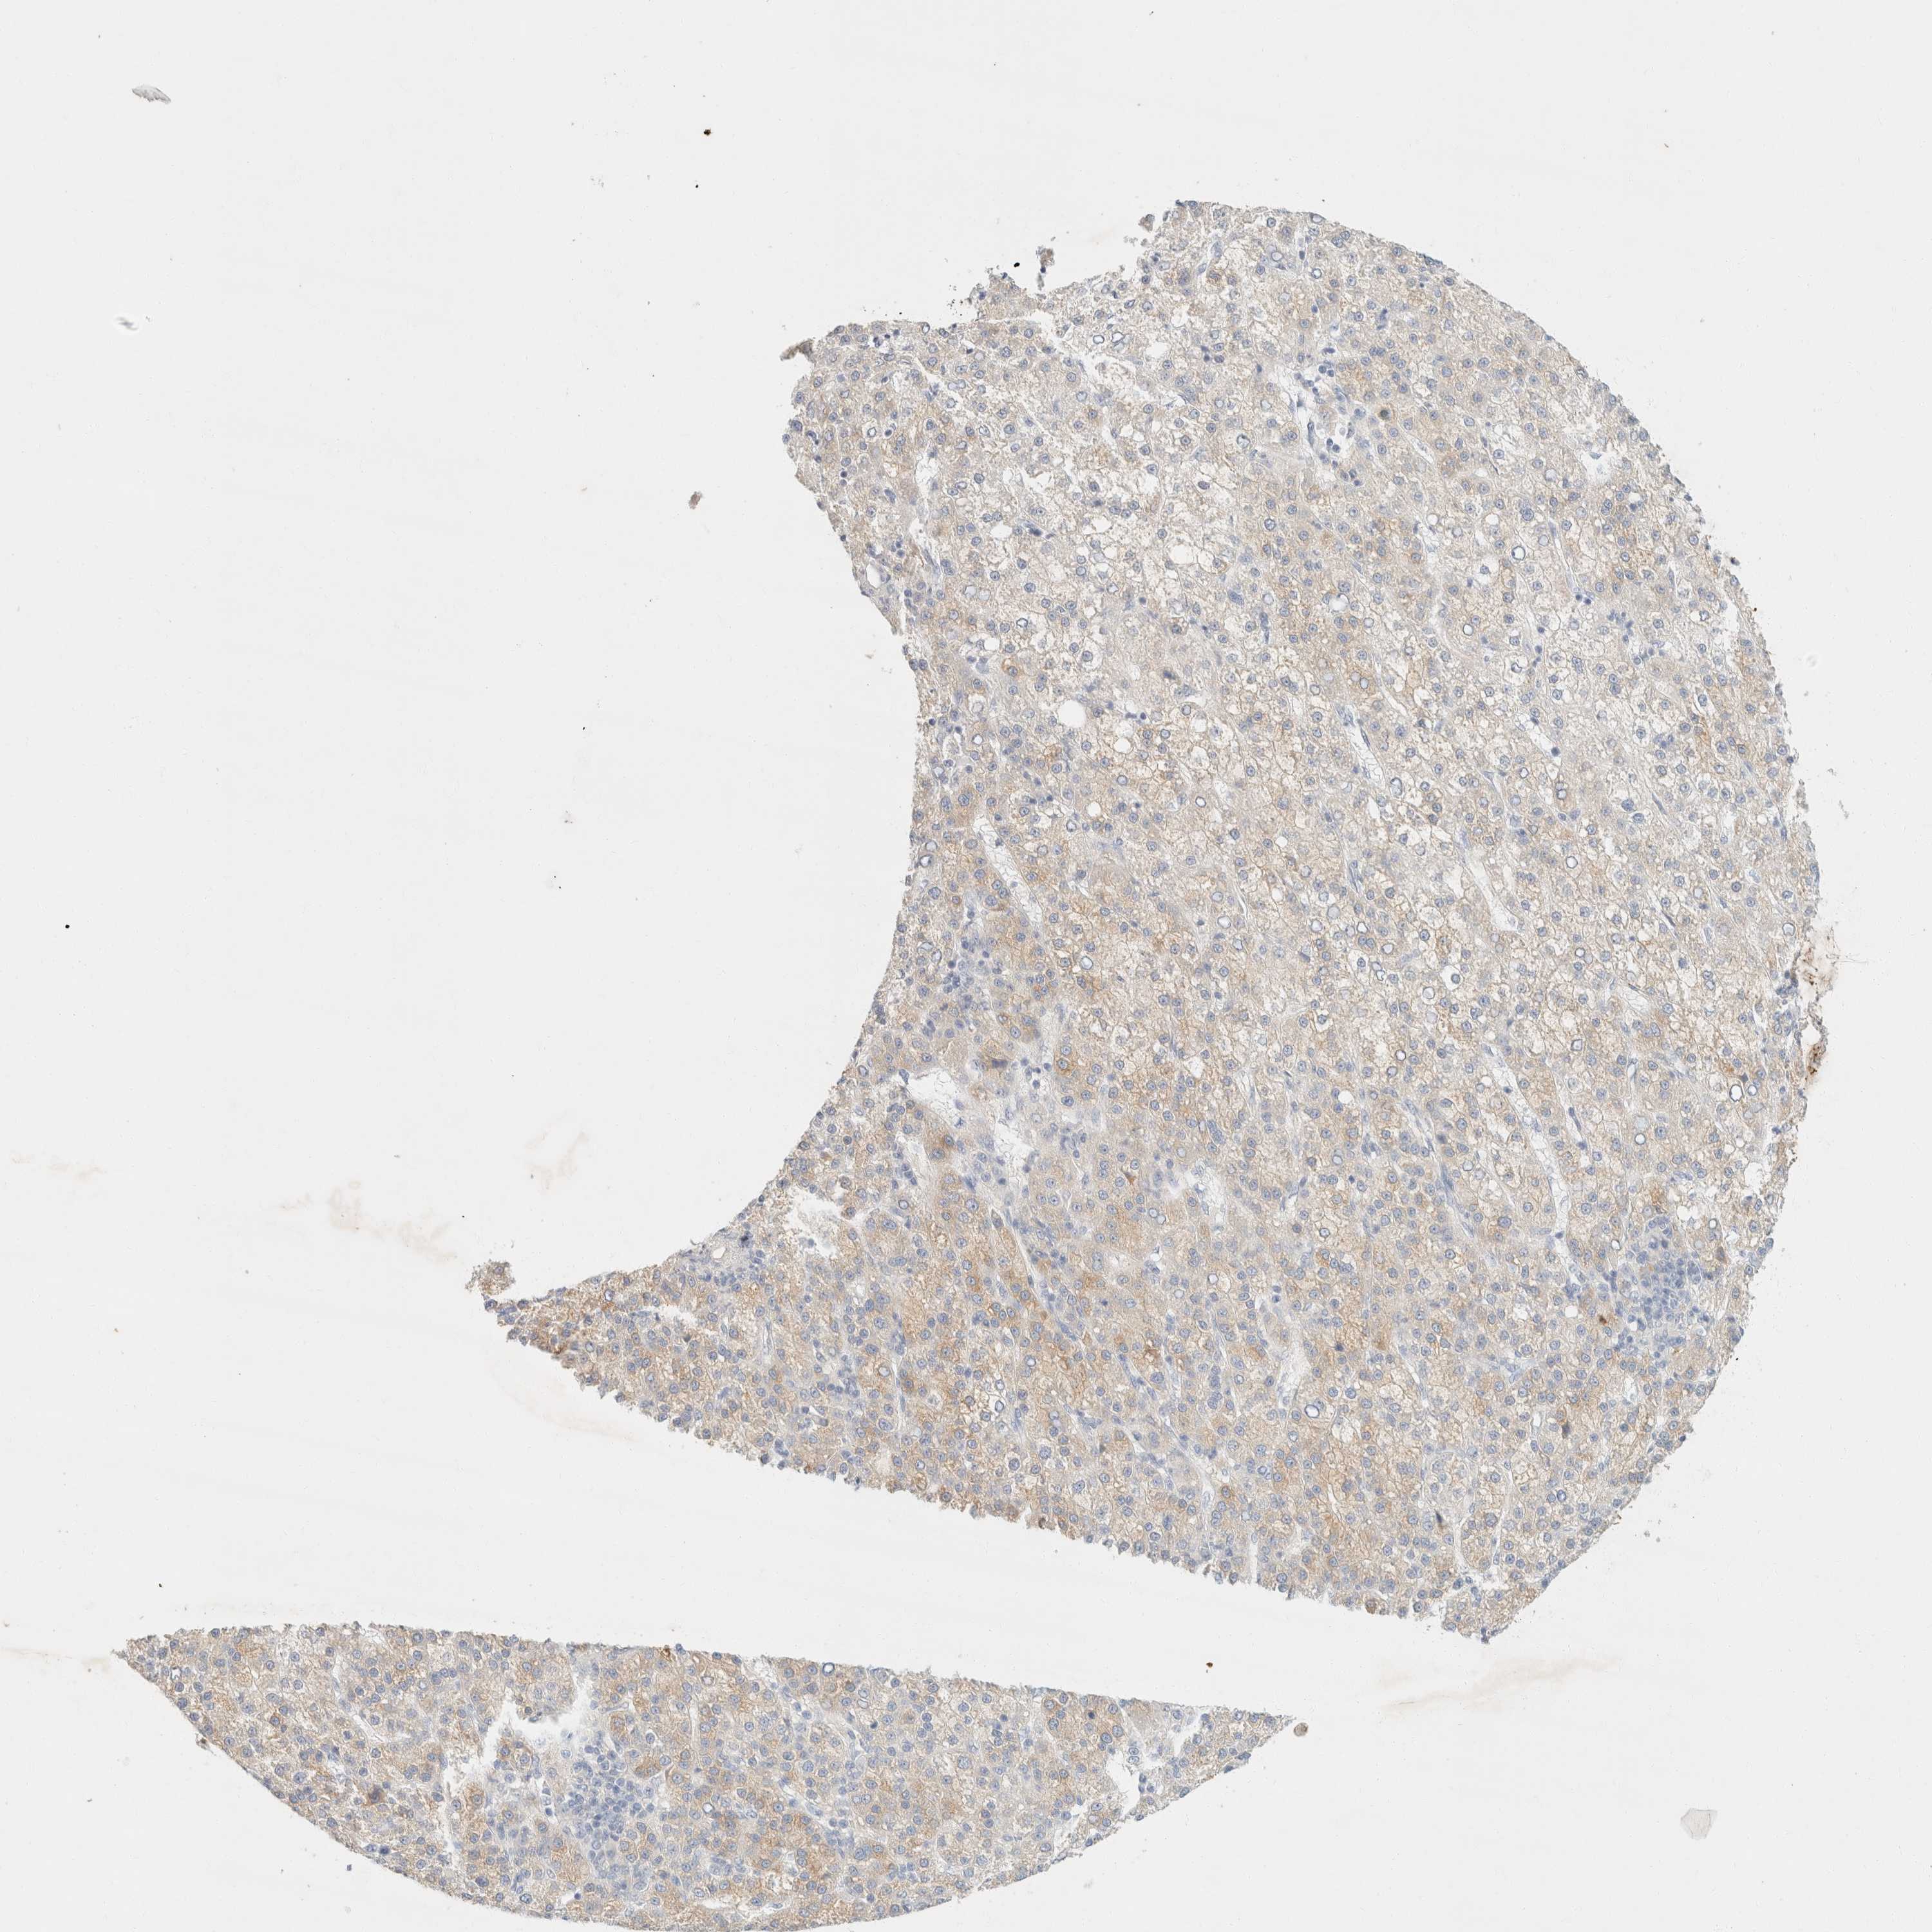

LIVER CANCER - Protein expressioni

A mouse-over function shows sample information and annotation data. Click on an image to view it in a full screen mode. Samples can be filtered based on level of antibody staining by selecting one or several of the following categories: high, medium, low and not detected. The assay and annotation is described here.

Note that samples used for immunohistochemistry by the Human Protein Atlas do not correspond to samples in the TCGA dataset.

Antibody stainingi

Antibody staining in the annotated cell types in the current human tissue is reported as not detected, low, medium, or high, based on conventional immunohistochemistry profiling in selected tissues. This score is based on the combination of the staining intensity and fraction of stained cells.

Each image is clickable and will lead to virtual microscopy that enables deeper exploration of all samples and also displays staining intensity scores, fraction scores and subcellular localization as well as patient and tissue information for each sample.

Antibody HPA023694

Staining

High

Medium

Low

Not detected

Intensity

Strong

Moderate

Weak

Negative

Quantity

>75%

75%-25%

<25%

None

Location

Nuclear

Cytoplasmic/membranous

Cytoplasmic/membranous,nuclear

Cholangiocarcinoma

Carcinoma, Hepatocellular, NOS